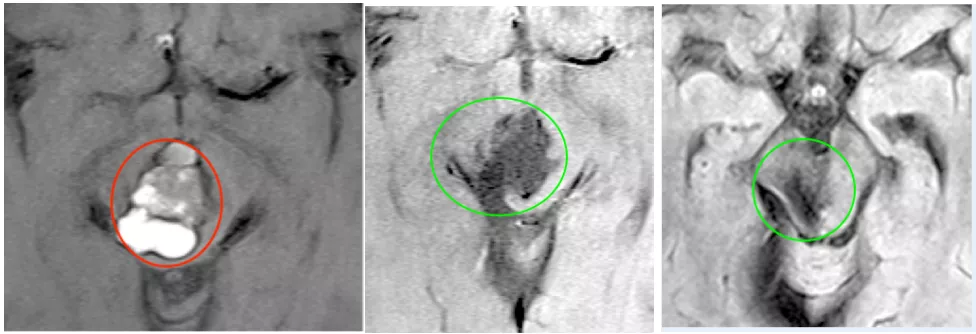

在这样的理念下,很快,一场手术正式开始。术中行幕下小脑上入路,实现肿瘤全切,无脑出血、脑水肿等损伤,而入脑干切除病变的切口仅有1.1CM,在毫厘之间全切巨大海绵状血管瘤。